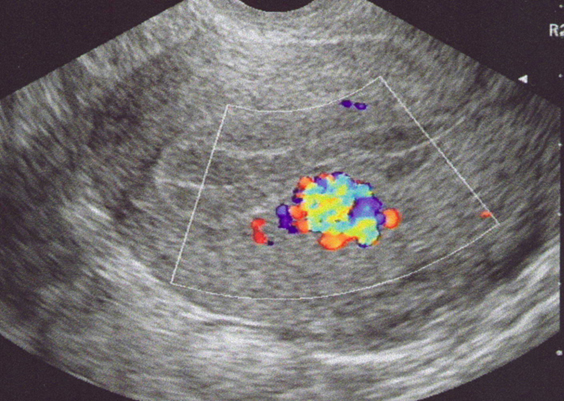

Fistule artério-veineuse au sein de l’endomètre après curetage (Doppler couleur) (Cliché : Dr. C. TALMANT)